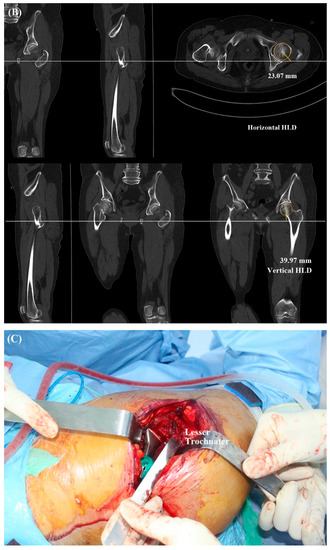

| 3-D HLD | - | 45.9 ± 3.6 | N/A |